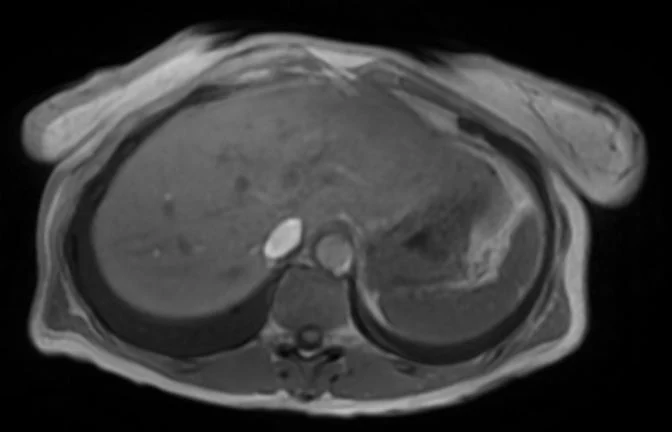

Eksempler på MR Scanninger

Denne højteknologiske metode er særligt velegnet til at visualisere det bløde væv i bughulen og kan afsløre selv mikroskopiske forandringer i levervævet. Scanningen giver et holistisk billede af hele leverregionen inklusive galdeblære, bugspytkirtel og galdegange.

For optimal diagnostik anvender vi i særlige tilfælde et leverspecifikt kontrastmiddel, der markant forbedrer muligheden for at differentiere mellem normalt levervæv og potentielle sygdomsforandringer.